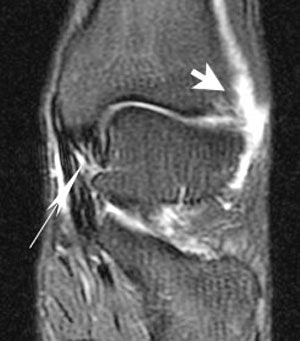

| Coronal FSEIR shows fluid (short arrow) at the anterolateral aspect of the ankle related to the syndesmosis sprain. It also demonstrates sprain of the deltoid ligament (long arrow). |